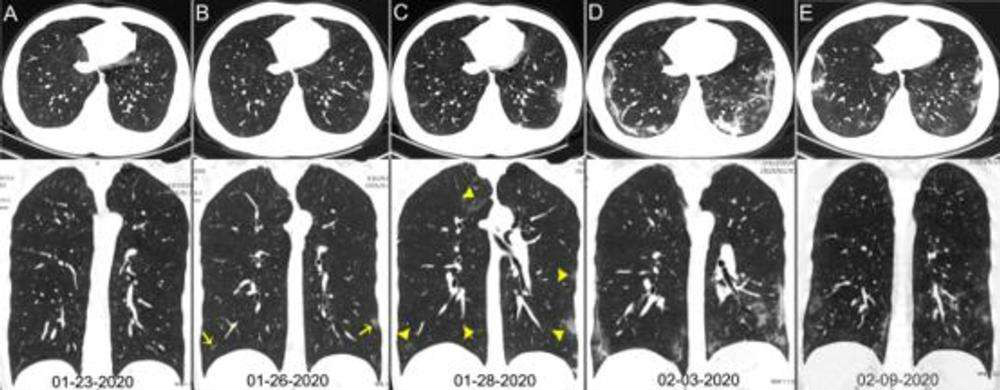

Através de radiografias pode ser mais difícil diagnosticar os danos no pulmão de um portador do covid-19. Porém, as tomografias mostram claramente os estragos feitos, como essas realizadas por uma equipe médica responsável pelo estudo que analisou pacientes de Wuhan, na China.

Crédito: Reprodução

As imagens mostram claramente — para especialistas — a evolução da pneumonia. Por isso, os pesquisadores concluíram que o raio-x de tórax não é o exame ideal para diagnóstico da nova doença, mas sim a tomografia computadorizada. Esse último deve ser usado em caso de dúvidas na hora do diagnóstico correto do covid-19, se o médico achar necessário.